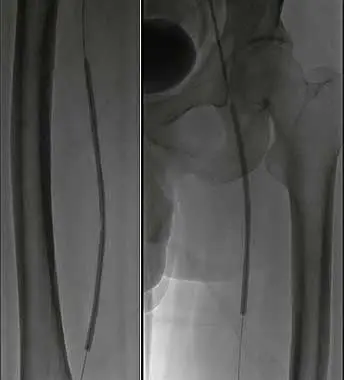

2、建立通路換入6F長鞘,遠端位于左股淺動脈。配合導絲導管技術通過左股淺動脈狹窄閉塞段。

3、減容:交換V-18導絲,以6F Rotarex旋切導管于左股淺動脈閉塞處減容。